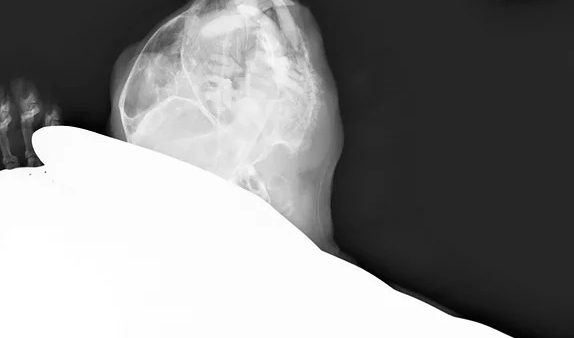

Case #003: 猫 交通事故 下顎骨骨折